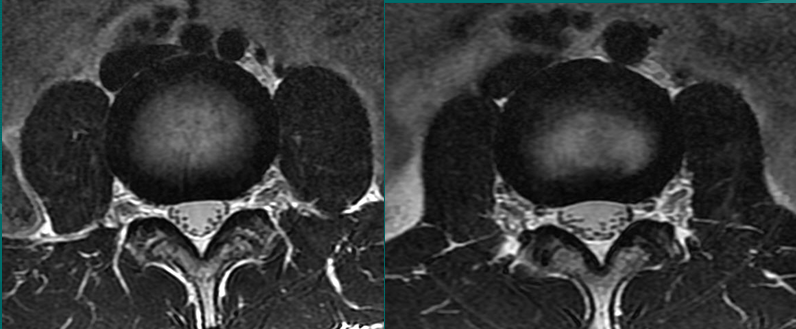

一个健康的45岁男性的L4椎间盘的轴状面观。

髓核区及周围的纤椎环区。

靠近L5神经根的椎间盘后缘的凹度,这是正常健康椎间盘的象征。

L4发出神经根更靠侧方一点。这就不难理解为什么如果有大的椎间盘突出或椎管狭窄,发出神经根L4及过往神经根L5将同时受压。

在此图中,可清楚地看到悬挂在硬膜囊内的细小的神经根(L5神经根及S1神经根),它们以不完全有绪地状态排列着。注意,神经孔是很开阔的(浅黄色区),表明没有因邻近椎间关节问题形成在的椎管狭窄。T2加权象对于察看退化性椎间盘病是最好的,因为T2像将富含水份的结构表现为亮白色, 含水少的区域表现为黑色。